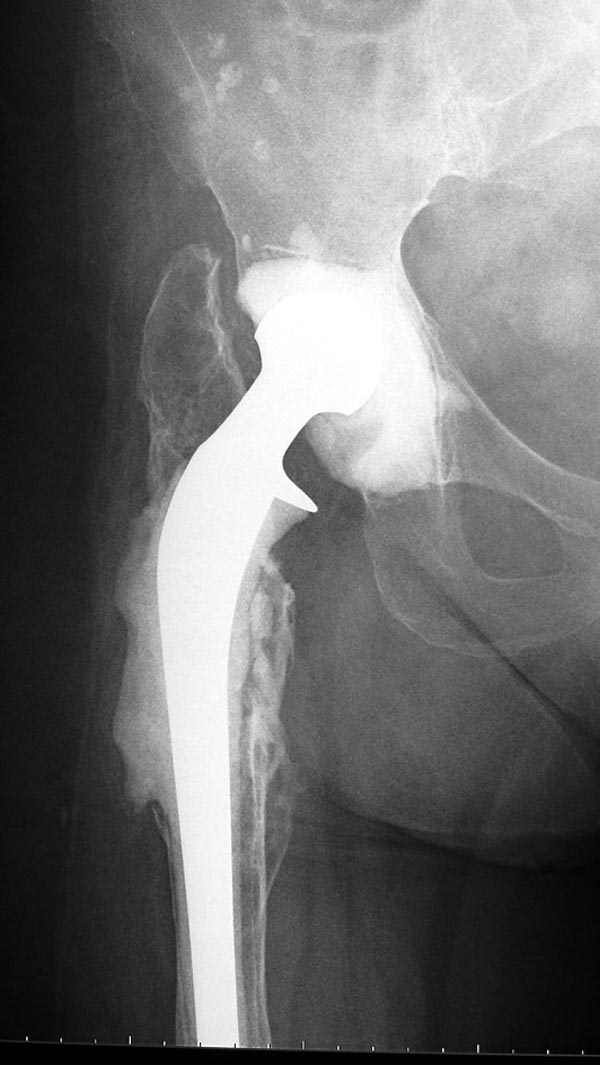

В вертлужную полость устанавливается цемент и головкой протеза выдавливается выемка, т.е. создается место для головки. В проксимальное бедро устанавливается заранее подготовленный цементный бедренный компонент.

Через пару месяцев после улучшения мягкотканой

кондиции можно приступить к окончательному протезу.

Следующий этап восстановление применением Blade Plate. Универсальный имплант и сегодня является уникальным по механическим характеристикам для восстановления проксимального отдела бедра где имеется сложная биомеханика.

Имеющиеся 130 градусные для вальгуса пластины от

Synthes короткие всего на две дырки, выход, обычная длинная 95 градусная Blade Plate разгибается до 105-110 градусов. Металл трудно поддается деформации, и его не согнуть между тепловой батереей в операционной, надо подготовить заранее после предварительного нагрева в механической мастерской.

Проведя клинок горизонтально в шейку, и соединив с

диафизом бедра создаем небольшой вальгус, тем самым увеличиваем длину конечности. Образовавшийся дефект кости надо заполнить блоком цемента, который предупреждает инфицирования и дает устойчивость конструкции. После затихания процесса можно приступить ко вторичному заполнению аутокостью или можно применить костную массу из того же местного костного регенерата.